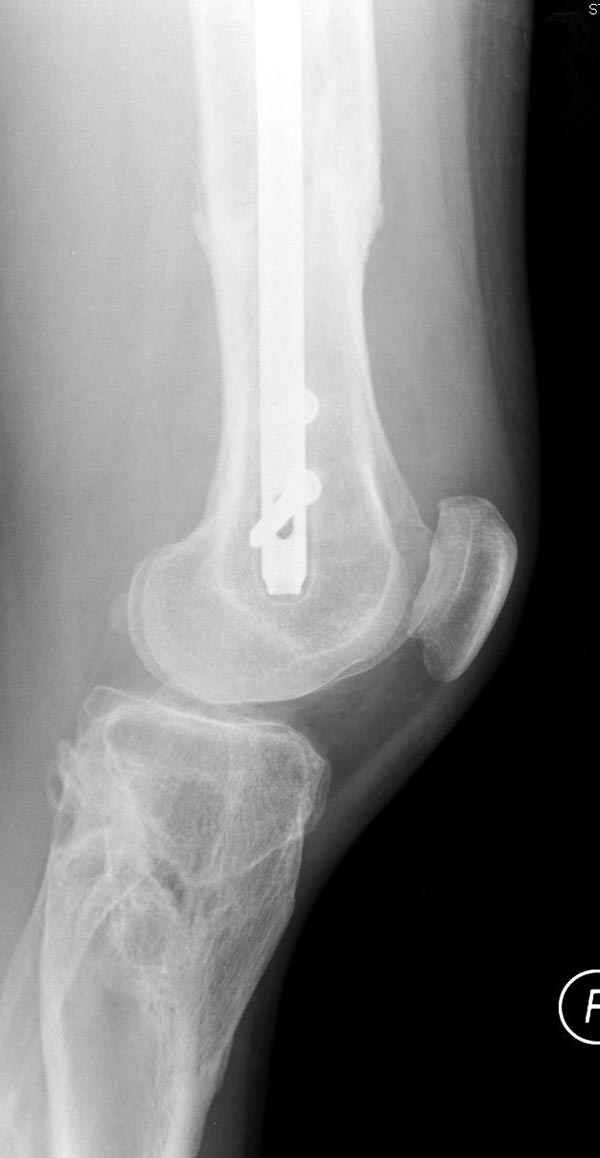

Замена реконструктивного штифта “Custom made Nail” с антибиотиком (рис №5, №6),

после промывки канала с рассверливанием внутреннего кортекса, через 4 недели антибиотический штифт удалили, оспалителный процесс остановлен и бедро сросся.

На следующий день произвели интрамедуллярный остеосинтез: этапы во время операции (рис №8, №9)

и последующих снимках (рис №10, 11, 12, 13) перелом сростается и передвигается с полной нагрузкой.